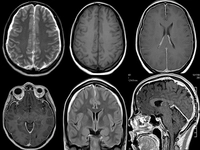

Tanı YöntemleriAkciğer tümörü tanısı, hastanın belirtileri ve fiziksel muayenesi ile başlayarak çeşitli testler ile devam eder. Tanı yöntemleri arasında: